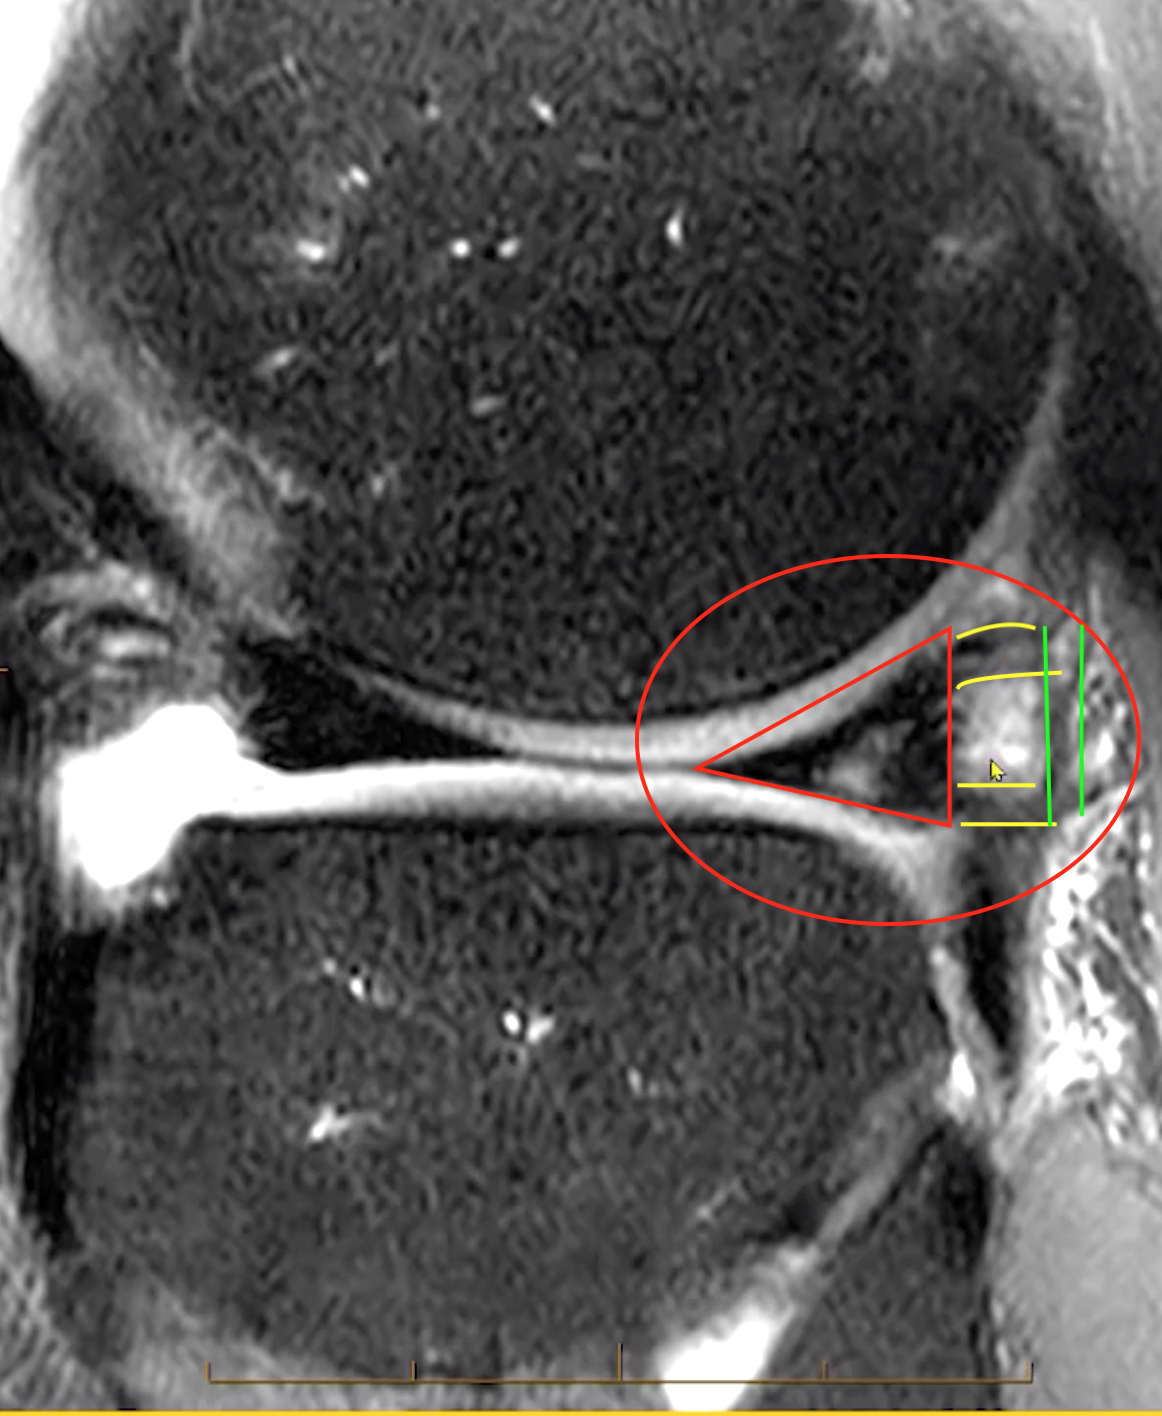

• Coronal width >14 mm or

• 3+ sagittal 5mm images

Meniscus Extrusion

• Meniscal extrusion is diagnosed as the mensicus relative to the tibia, not the femur

• Medial meniscus

• The meniscus and tibia should be directly in line an any extrusion of the meniscus past the lateral aspect of the tibia is abnormal

• Lateral meniscus

• Can have minimal (1 mm or less) beyond the lateral tibial plateau and be normal